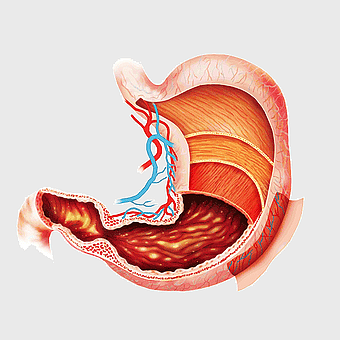

human digestive system anatomy, gastrointestinal tract illustration, stomach muscular layer, abdominal organ diagram, digestive health education, medical biology study, internal human body structures -

stomach illustration, full stomach anatomy, abdominal organ depiction, human digestive system, gastroenterology graphics, medical illustration artwork, digestive health visual -

human stomach anatomy, gastrointestinal tract illustration, small intestine diagram, peptic ulcer disease, digestive system health, internal organ function, pink medical graphic -